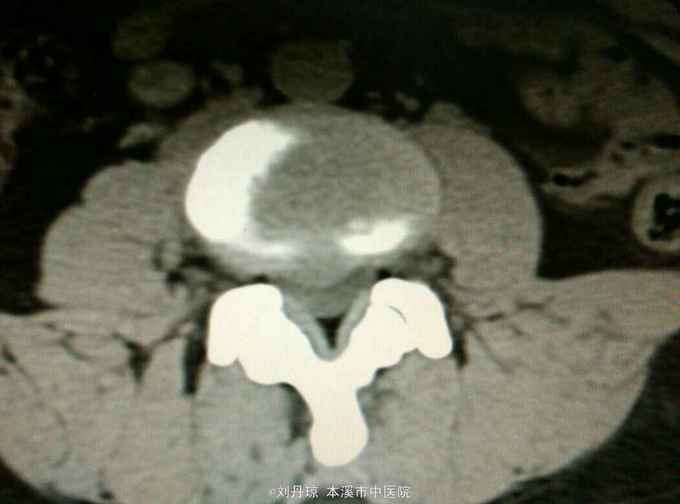

腰部疼痛伴右下肢放射痛麻木感1年,加重1月。患者1年前劳累后感到腰部疼痛伴右下肢放射痛麻木感,近1月病情加重来诊。

查体:L3—S1棘突右旁压痛阳性。直腿抬高实验左70度,右40度。 直腿抬高加强实验左侧阴性,右侧阳性。腰椎功能障碍。 辅查:CT: L3—S1椎间盘突出。

诊断:腰椎间盘突出症 治疗:针灸、雷火灸、中药熏药治疗、小针刀治疗、骶管注射治疗、营养神经药物治疗、脱水药物治疗,当归地黄饮加味。